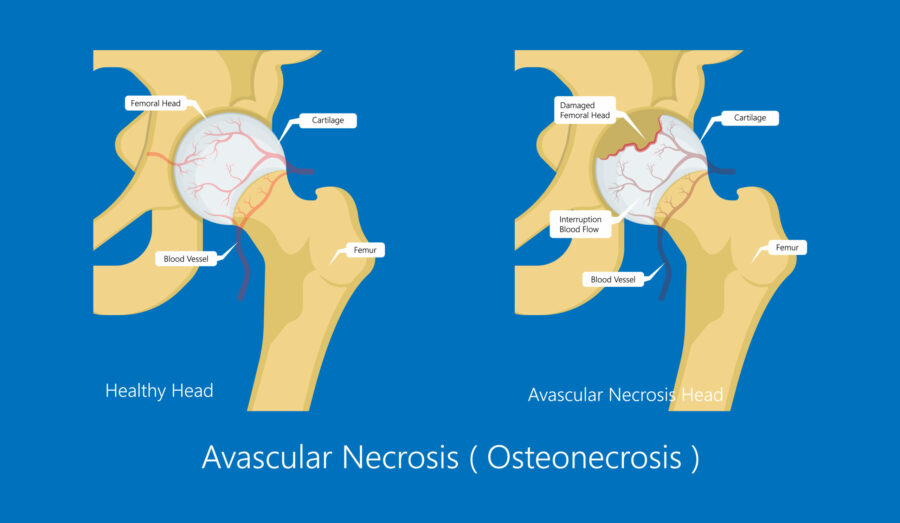

Avascular necrosis (AVN) is a medical condition that happens when there is very little, or no blood supply to your bone. As a result, parts of your bone tissue may deteriorate, break away and die. AVN can affect any bone in your body, but is most common in the bones near your joints and the hip joint is the most common joint affected.

The cause of AVN is a lack of blood getting to your bones. As a result, your bones don’t get the nutrients they need to stay healthy or repair themselves, so they slowly deteriorate and die.